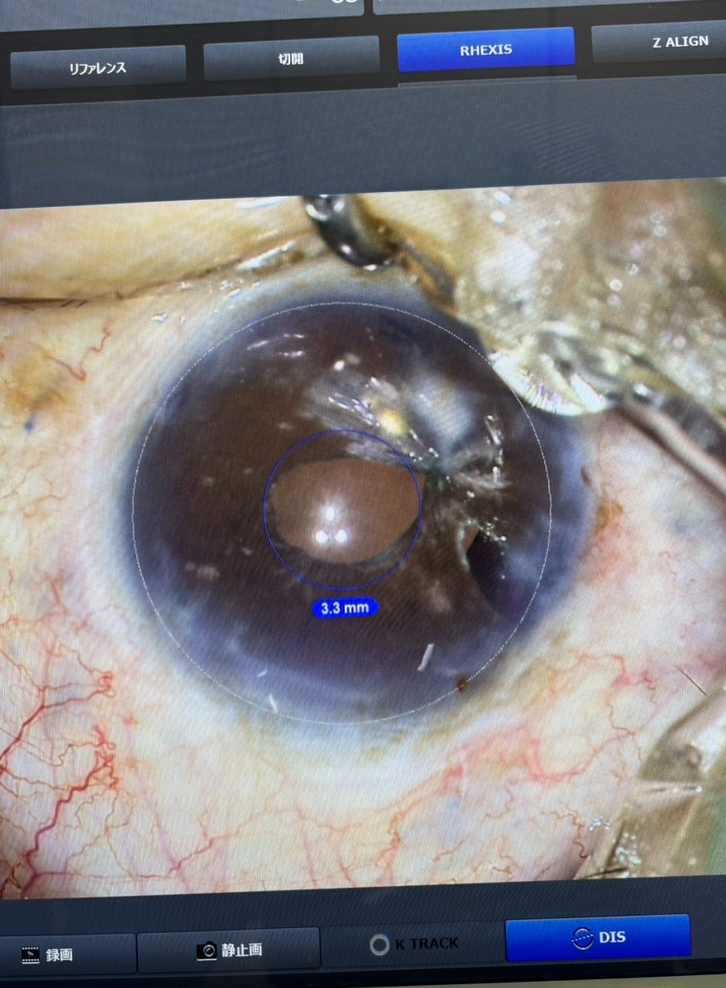

今日の手術では、外傷後の瞳孔散大で眩しさによる見えにくさを感じている男性の患者さんで、瞳孔を縫い縮まる虹彩縫合がありました。元々入っていた眼内レンズが混濁したことで、昨年、レンズの入れ換え(強膜内固定)と虹彩縫合を行っていましたが、術後、瞳孔の閉じ方が弱くなり、次第に眩しさが強くなり、手術直後の方が見えたと感じるようになったため、また虹彩を縫って欲しいと頼まれました。はい、分かりましたと二つ返事で答えたいところでしたが、虹彩はとても柔らかく繊細な組織な上に、角膜と虹彩の間の3mmほどのスペースで針を使った操作をしなければなりませんし、外傷後で部分的にボロボロになっているところを縫うことは簡単なことではありません。場合によっては予期せぬ針の動きによって、虹彩が千切れ、余計に瞳孔が拡がってしまう恐れもありますし、角膜の内皮細胞を痛めてしまうと、角膜の濁りを生じてかえって見えにくくなってしまう心配もあります。なので、無理に手術しなくてもよいのではとお話していましたが、そのリスクを承知いただいた上で、ご本人の希望を踏まえて手術させていただきました。実際、手術はちょっと大変でしたが、なんとか無事虹彩を縫え、5mmくらいの瞳孔が3mmちょっとまで縮んでくれ、とりあえずは大きなトラブルなく終えられてよかったです。